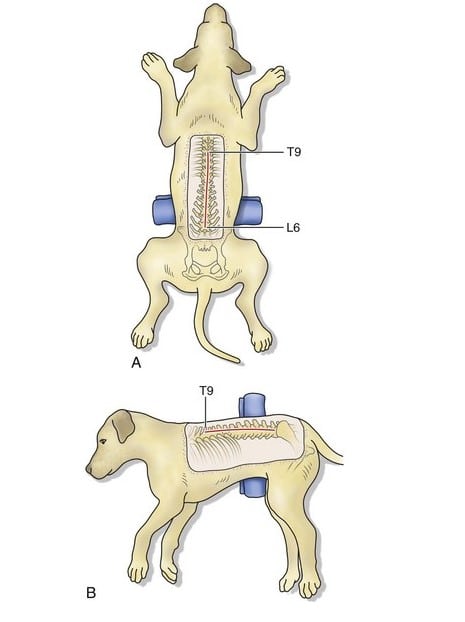

Types of Spine & Herniated Disc Surgery

Hemilaminectomy (Most Common)

- Removes part of the vertebral bone

- Relieves pressure on the spinal cord

- Common for thoracolumbar IVDD

What Happens During Surgery?

- General anesthesia

- Surgical exposure of the affected spinal segment

- Removal of disc material compressing the spinal cord

- Spinal stabilization (if required)

- Closure and intensive monitoring